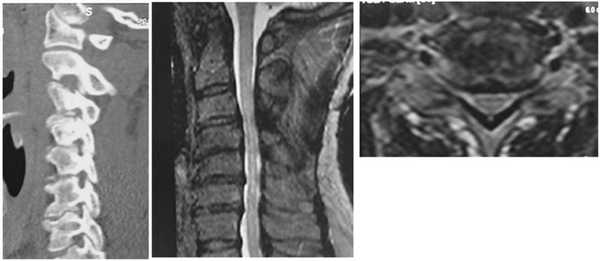

Чувствительные расстройства в виде гипестезии с уровня СV дерматома, более выраженные в дистальных отделах правой руки и левой ноги. Глубокий смешанный тетрапарез (вялый — до 1 балла в руках и спастический — до 3 баллов в ногах). Сухожильные рефлексы на руках (бицепс, карпорадиальный) резко ослаблены. На нижних конечностях рефлексы повышены, больше слева. Патологические рефлексы на ногах. Брюшные рефлексы симметрично повышены. Данные инструментальных исследований представлены на рис. 6. Рис. 6. МСКТ, МРТ позвоночника. Дегенеративный полисегментарный стеноз позвоночного канала, фораминальный стеноз — тип, А деформации позвоночника.

Выполнена операция: транспедикулярная фиксация СIII—СIV—СV—СVI—СVII, ламинэктомия СIV, СV, СVI, резекция дужек СIII—СVII, фораминэктомия СIII—СIV—СV—СVI с обеих сторон, декомпрессия спинного мозга и корешков на уровне СV—СVI (рис. 7). Рис. 7. МСКТ-контроль (сагиттальная и аксиальная проекции).